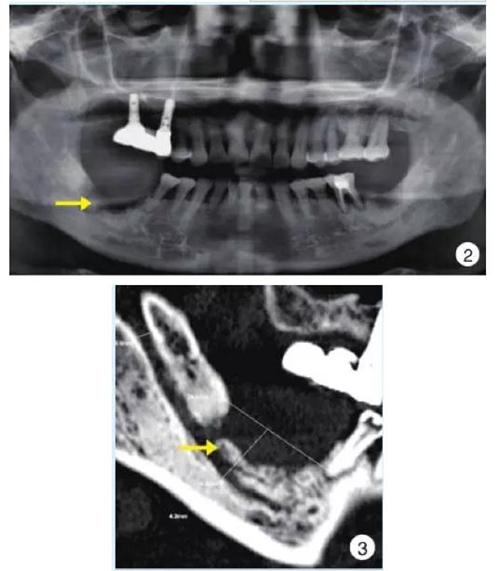

影像學(xué)早期無明顯變化,后期典型表現(xiàn)為局部片狀骨密度增高影以及不規(guī)則的骨吸收影像、死骨形成,偶爾可見骨膜反應(yīng);伴病理性骨折時(shí)可見骨折線。

2.jpg